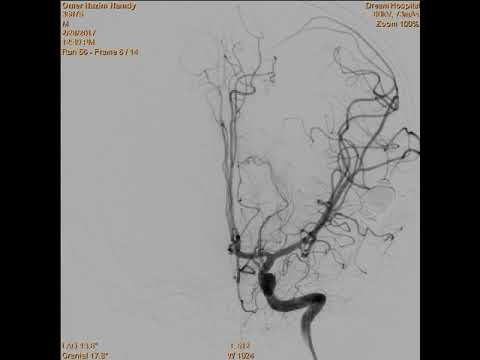

Hellow guys, Welcome to my website, and you are watching Nav-guided transsylvian approach & microsurgical resection of a deep left temporal low-grade AVM. and this vIdeo is uploaded by American Association of Neurological Surgeons at 2017-08-10T14:21:52-07:00. We are pramote this video only for entertainment and educational perpose only. So, I hop you like our website.